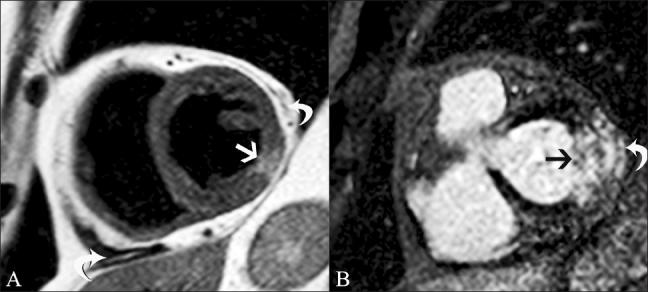

磁共振成像在评估心电图ST段抬高患者中的应用价值。

Utility of magnetic resonance imaging in the evaluation of patients with ST segment elevation on an electrocardiogram.

ST segment elevation is an important electrocardiographic (ECG) change that is typically found in acute myocardial infarction, but may also be seen in a variety of other conditions. MRI plays an important role in the evaluation of these patients. MRI not only establishes the diagnosis, which is essential for appropriate management, but also helps in the assessment of other factors that are important for risk stratification. In this review, we discuss the common and uncommon causes of ST segment elevation and the role of MRI in the evaluation of these disease processes.

摘要